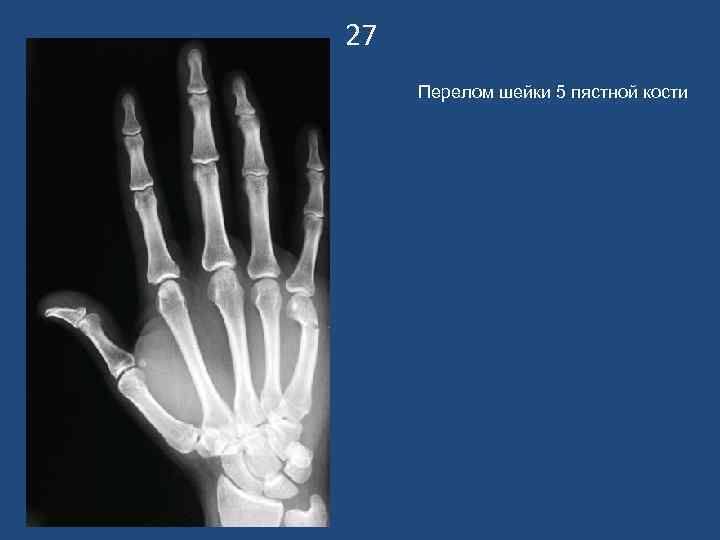

27 Перелом шейки 5 пястной кости